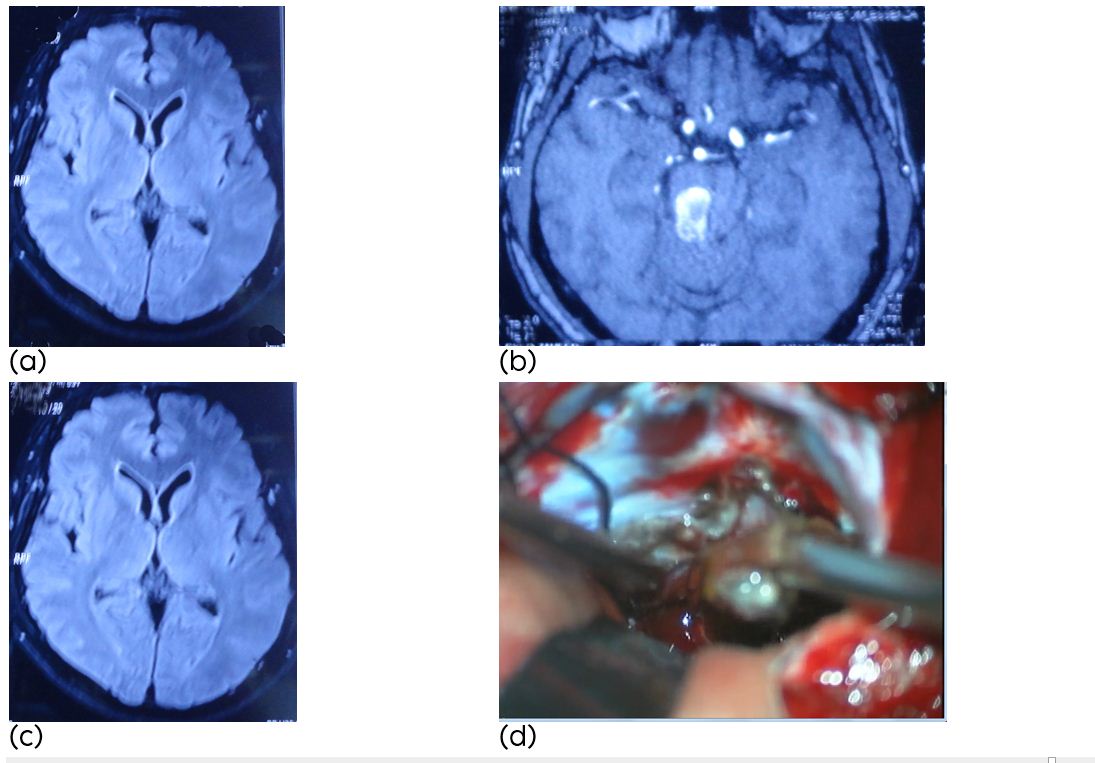

A 53-year-old man presented with acute onset of headache associated with a left hemi paresis, gait disturbance, and lower cranial nerve disturbances with one episode of haemorrhage. Brain MRI showed a cavernous malformation located in the pons & midbrain (Figure 1). A combined sub occipital craniectomy and occipital craniotomy, the pons & midbrain were exposed showing a circumscribed red-bluish area. After evacuation of the haematoma, the cavernous malformation was identified and completely resected. Last follow up at six months showed mild left hemiparesis and left mild cerebellar signs whereas disturbances of the lower cranial nerves had resolved completely (Rankin score 2). The haematoma is removed and the cavernous malformation is identified. After resection of the lesion the cavity is collapsed. Hemosiderin stained gliotic tissue surrounding the lesion is left behind.

Figure 1a,b,c: (a-c) Axial MR image showing a cavernous malformation of the pons after the first haemorrhage, (d) Intraoperative photograph: After exposure the bulging aspect of the right lateral pons and subpial hemosiderin staining is visible.